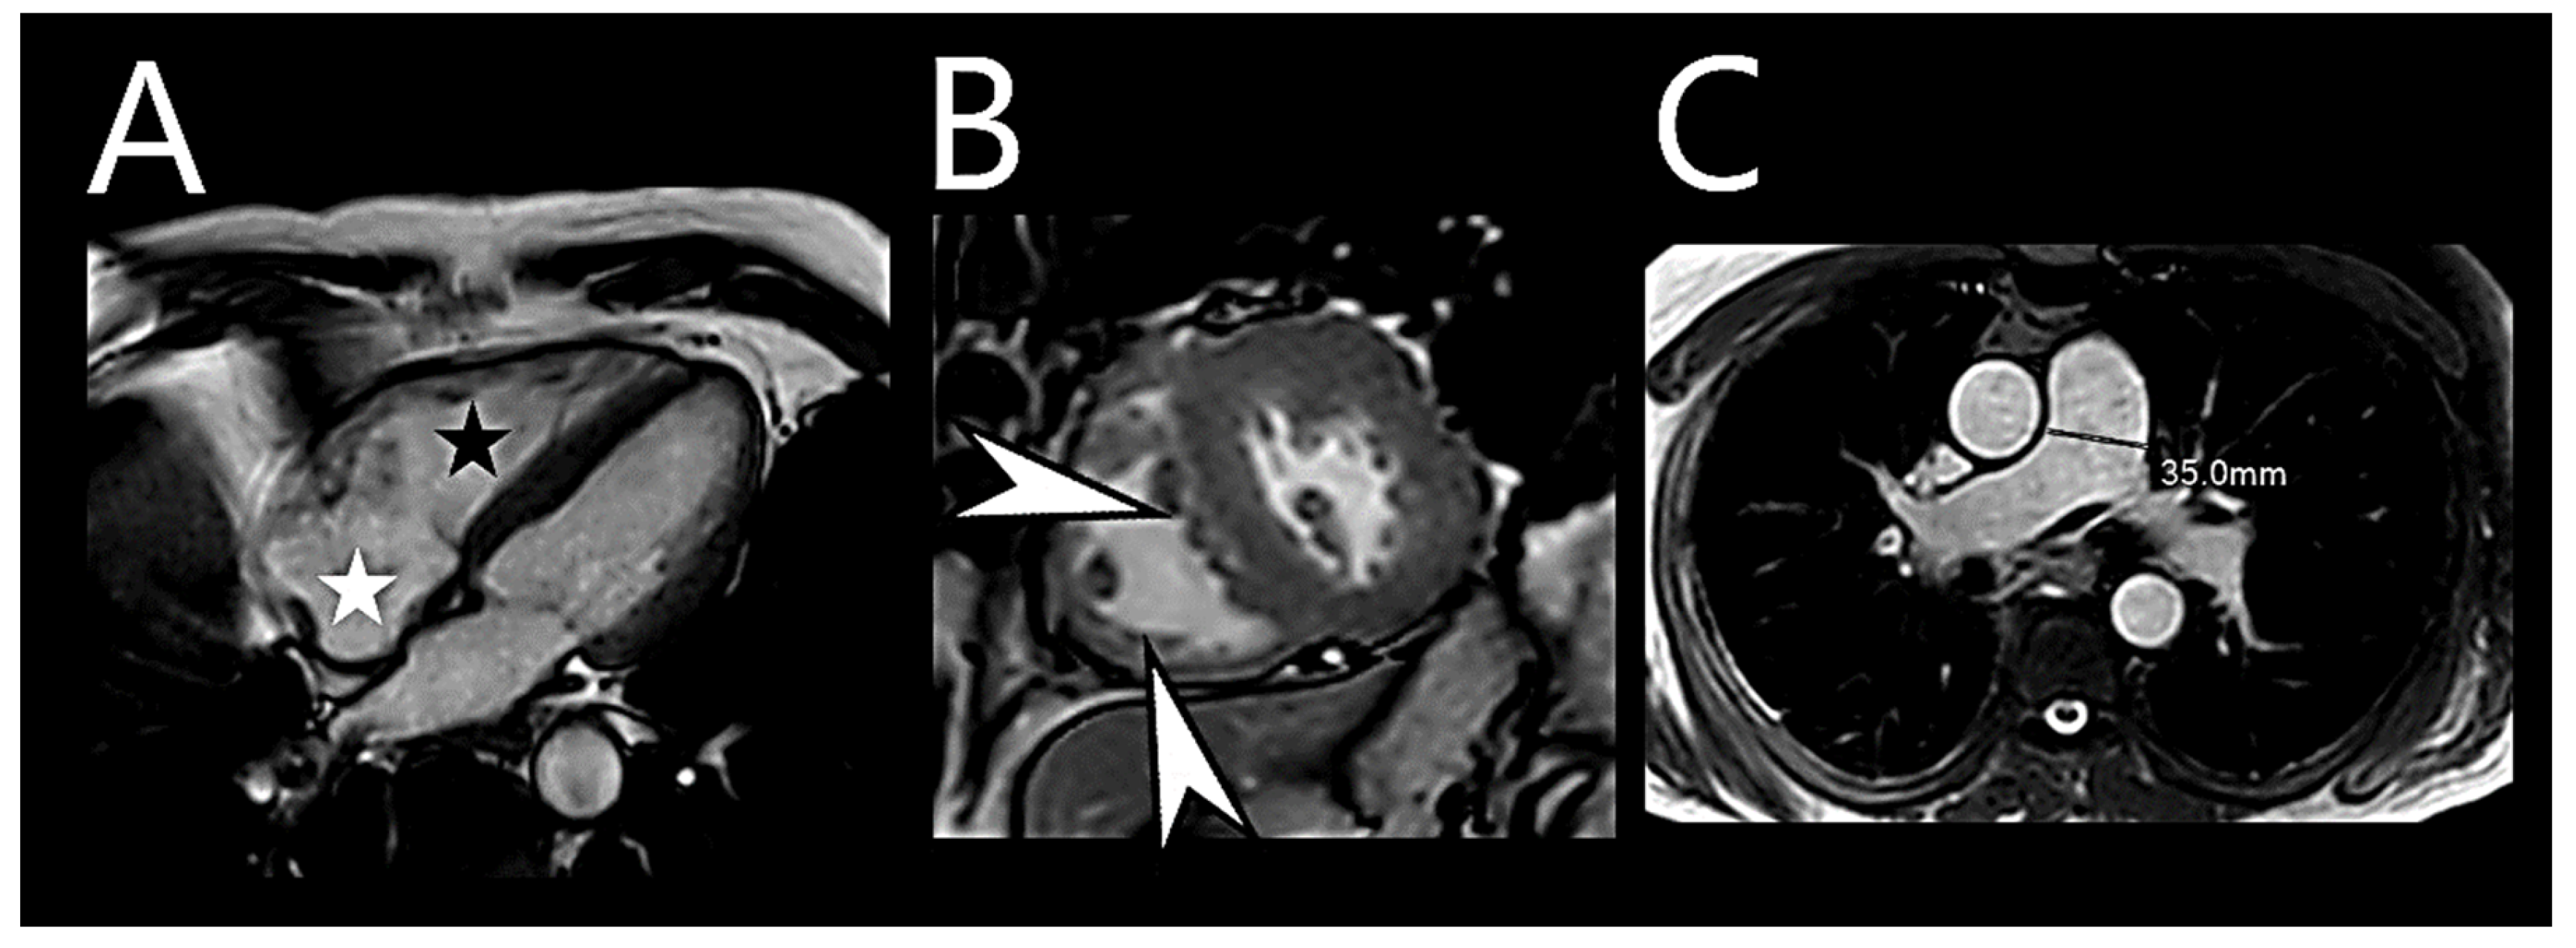

6.6. Cardiac Magnetic Resonance Imaging

- Saba, T.S.; Foster, J.; Cockburn, M.; Cowan, M.; Peacock, A.J. Ventricular mass index using magnetic resonance imaging accurately estimates pulmonary artery pressure. Eur. Respir. J. 2002, 20, 1519–1524. [Google Scholar] [CrossRef] [PubMed]

- Dellegrottaglie, S.; Sanz, J.; Poon, M.; Viles-Gonzalez, J.F.; Sulica, R.; Goyenechea, M.; Macaluso, F.; Fuster, V.; Rajagopalan, S. Pulmonary Hypertension: Accuracy of Detection with Left Ventricular Septal-to–Free Wall Curvature Ratio Measured at Cardiac MR. Radiology 2007, 243, 63–69. [Google Scholar] [CrossRef] [PubMed]

- Shehata, M.L.; Harouni, A.A.; Skrok, J.; Basha, T.A.; Boyce, D.; Lechtzin, N.; Mathai, S.C.; Girgis, R.; Osman, N.F.; Lima, J.A.C.; et al. Regional and Global Biventricular Function in Pulmonary Arterial Hypertension: A Cardiac MR Imaging Study. Radiology 2013, 266, 114–122. [Google Scholar] [CrossRef]

- Freed, B.H.; Collins, J.D.; François, C.J.; Barker, A.J.; Cuttica, M.J.; Chesler, N.C.; Markl, M.; Shah, S.J. MR and CT Imaging for the Evaluation of Pulmonary Hypertension. JACC Cardiovasc. Imaging 2016, 9, 715–732. [Google Scholar] [CrossRef]

- Swift, A.; Capener, D.; Alex, R.; Charlie, E.; Robin, C.; Jim, W.; David, K. Prognostic value of MRI in pulmonary arterial hypertension: Early and late predictors. 43 Pulmonary Circulation and Pulmonary Vascular Disease. Eur. Respir. Soc. 2015, 46, OA3523. [Google Scholar] [CrossRef]

- Swift, A.J.; Capener, D.; Johns, C.; Hamilton, N.; Rothman, A.; Elliot, C.; Condliffe, R.; Charalampopoulos, A.; Rajaram, S.; Lawrie, A.; et al. Magnetic Resonance Imaging in the Prognostic Evaluation of Patients with Pulmonary Arterial Hypertension. Am. J. Respir. Crit. Care Med. 2017, 196, 228–239. [Google Scholar] [CrossRef]

- Lewis, R.A.; Johns, C.S.; Cogliano, M.; Capener, D.; Tubman, E.; Elliot, C.A.; Charalampopoulos, A.; Sabroe, I.; Thompson, A.A.R.; Billings, C.G.; et al. Identification of Cardiac Magnetic Resonance Imaging Thresholds for Risk Stratification in Pulmonary Arterial Hypertension. Am. J. Respir. Crit. Care Med. 2020, 201, 458–468. [Google Scholar] [CrossRef] [PubMed]

- Swift, A.J.; Rajaram, S.; Hurdman, J.; Hill, C.; Davies, C.; Sproson, T.W.; Morton, A.C.; Capener, D.; Elliot, C.; Condliffe, R.; et al. Noninvasive Estimation of PA Pressure, Flow, and Resistance With CMR Imaging. JACC Cardiovasc. Imaging 2013, 6, 1036–1047. [Google Scholar] [CrossRef] [PubMed]

- Lungu, A.; Wild, J.M.; Capener, D.; Kiely, D.G.; Swift, A.J.; Hose, D.R. MRI model-based non-invasive differential diagnosis in pulmonary hypertension. J. Biomech. 2014, 47, 2941–2947. [Google Scholar] [CrossRef] [PubMed]

- Whitfield, A.J.; Solanki, R.; Johns, C.S.; Kiely, D.; Wild, J.; Swift, A.J. MRI Prediction of Precapillary Pulmonary Hypertension according to the Sixth World Symposium on Pulmonary Hypertension. Radiology 2020, 294, 482. [Google Scholar] [CrossRef]

- Alkhanfar, D.; Dwivedi, K.; Alandejani, F.; Shahin, Y.; Alabed, S.; Johns, C.; Garg, P.; Thompson, A.A.R.; Rothman, A.M.K.; Hameed, A.; et al. Non-invasive detection of severe PH in lung disease using magnetic resonance imaging. Front. Cardiovasc. Med. 2023, 10, 1016994. [Google Scholar] [CrossRef] [PubMed]

- Alenezi, F.; Covington, T.A.; Mukherjee, M.; Mathai, S.C.; Yu, P.B.; Rajagopal, S. Novel Approaches to Imaging the Pulmonary Vasculature and Right Heart. Circ. Res. 2022, 130, 1445–1465. [Google Scholar] [CrossRef] [PubMed]